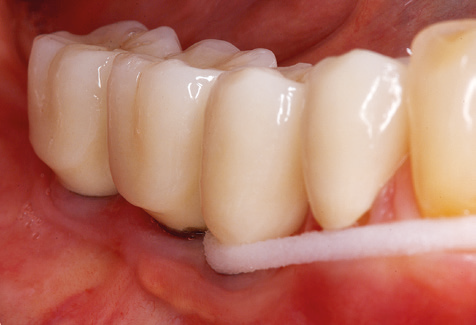

A 52-year-old patient presented in our clinic for the first time in 2004 following tooth loss in the third quadrant, expressing a desire for a new prosthetic restoration. Periodontal and radiological diagnostics revealed the need for extensive periodontological treatment. In addition, teeth 48, 28 and 27 were attributed a very poor prognosis and were subsequently extracted (Fig. 1). Following the successfully completed, systematic periodontological treatment, a fixed dental implant was inserted with the introduction of five implants in tooth regions 35, 36, 37, 46 and 47. Prosthetic treatment of the natural teeth was effected with veneered zirconium dioxide ceramic crowns; the implants were composed of two-piece, individual zirconium dioxide abutments and similarly veneered crowns made of a zirconium dioxide ceramic (Cercon base colored, Dentsply Sirona Lab). Definitive insertion of the prosthetic restoration occurred in 2005.

Following machine cleaning of the tooth and implant surfaces, the surfaces of the natural teeth are cleaned manually using standard hand instruments. When performing manual cleaning, particular attention must be given to maintaining the correct angle of application, appropriate sharpness, good support and working with the curette from apical to coronal. Either titanium or carbon curettes should be used for post-cleaning of the implant structures (Fig. 8). In addition to the use of ultrasonic devices, power jet devices can also be used in conservative dentistry. However, it must be taken into consideration that these procedures are not suitable for removing hard deposits and thus they cannot replace the use of hand instruments and ultrasonic instruments completely. In all cases, cleaning is followed by mechanical polishing of the accessible tooth and implant surfaces with polishing cups and polishing compounds (Fig. 9).

Standardised and regular risk-adapted care in the scope of SPT is the key to treatment success for the clinical long-term success in periodontically compromised patients. This is particularly true for patients fitted with implants following successfully completed periodontal treatment (Fig. 11a and b).